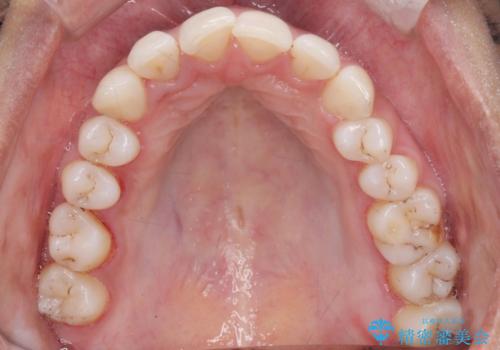

着色が気になる(エアフロー)

- 着色が気になるとの事で来院。

エアフローでしっかり着色を取り除きました。

着色が目立たなくなり大変満足して頂けました。